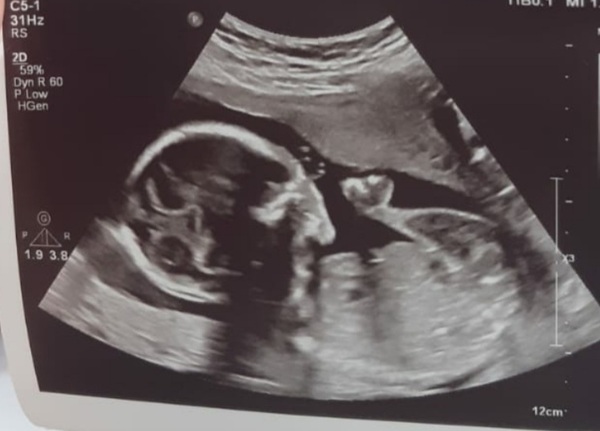

Help me figure out my scan? 20 weeks.

Hey all. Had 20 week scan last week at 20+3. I felt the sonographer was in a rush trying to get the job done very quickly, which is understandable, but she actually hurt me at times digging deep on my stomach trying to get measurements as she said she can't afford to have me coming back for another scan as they don't have enough slots, She didn't detail much and i could barely make out anything she was scanning, she didn't really explain anything and i didn't really get a proper look at the baby, she asked if i wanted a photo of baby, i said yes and this is what she took. I literally still can't make out what's what and where the face is? Maybe just a poor image, but can any one see any face, nose or lips? Or legs or feet? I can just see a chicken drum stick hahaaa! Can any one point me in the right direction 😂 the assistant did give me two but other isn't the best either.

It looks to me like it's slightly towards the back of the baby's head so you're not seeing the face in profile. The point of the scan is for them to check everything is okay though, not to get a decent image of the baby for the parents to take.